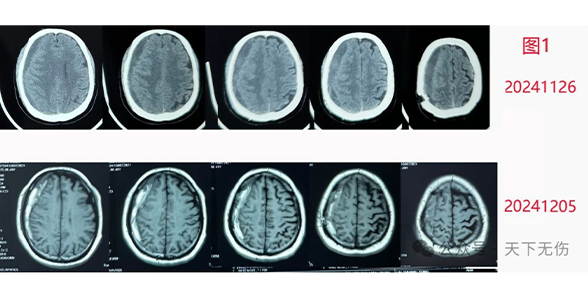

C先生,今年49岁,没有任何外伤,明确10月初有一次用力抬东西后眩晕感历史。1周后头疼头晕明显,到北京某医院就诊,确诊为慢性硬膜下血肿并接受了手术。11月26日复查确诊术后复发。医生建议他再做一次手术,他非常犹豫。多方咨询后,他的朋友向他推荐了我。我见他刀口处畸形愈合,头皮凹陷,知道他是疤痕体质,确实不适合再次开刀。药物治疗当然可行,但是,他的最近复查距离我门诊已经差不多半个月,因此建议他复查头磁共振。结果显示,他的血肿已经开始吸收。追问病史得知,他在10月接受手术后,医生给他用了阿托伐他汀钙(立普妥),我对比他两次影像给他看,确认血肿缩小,而且症状明显减轻。他十分激动。他是个至少1米八的堂堂西北汉子,却站起来连续给我鞠躬。说他因为近期失业,没有医保,这次看病花了很多钱,而我的治疗有望让他只花很少的钱就解决问题,非常感谢我。

H先生,74岁。10月初发生严重外伤,诊断为脑挫裂伤,颅内积气,左侧硬膜下血肿。因意识尚可,北京某医院没有给他做手术,11月09日复查见血肿液化,但症状逐步加重,出现走路不稳、嗅觉异常和全身异常感觉。非常焦虑。家人陪他到我门诊,他话很少,是家人代叙。因为距离他最近检查的头CT已经接近1个月没有复查了,我说服他去做个头部磁共振。2小时后我看到片子(图2),高兴地恭喜他已经痊愈。我还告诉他和他的家人,脑外科已经无需治疗。追问病史,才得知,他也是在医生建议下自服阿托伐他汀钙,而且服用了43天。得知不必再治疗的消息后,他们开始简直不敢相信,当再次确认后,一家人高兴地带着患者离开,不说话的这位患者,临走时居然也笑着开口向我表达致谢了。